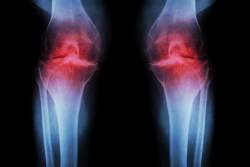

不治の病の一つの膝軟骨再生までどうにかなってしまった

スタンフォード・メディシンの科学者たちは、加齢関連のタンパク質(15-PGDH)を阻害することで膝軟骨を再生し、年配の動物の関節損傷を逆転させ、ACL様損傷後の関節炎を防ぐことができることを発見しました - 幹細胞を使用せずに。

関連する錠剤の初期安全性試験はすでに進行中であり、人間の軟骨再生に向けた本物の勢いを高めています。